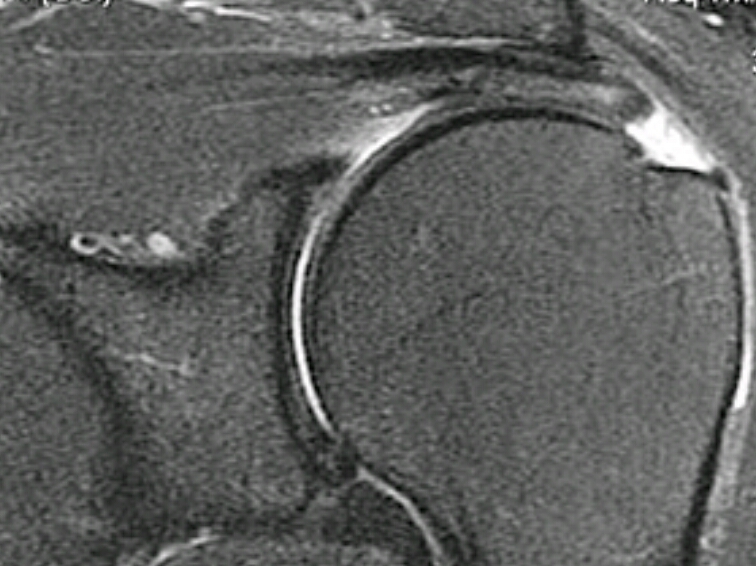

What type of image is this? (be specific)

what is the disease?

rotator cuff tear

T2